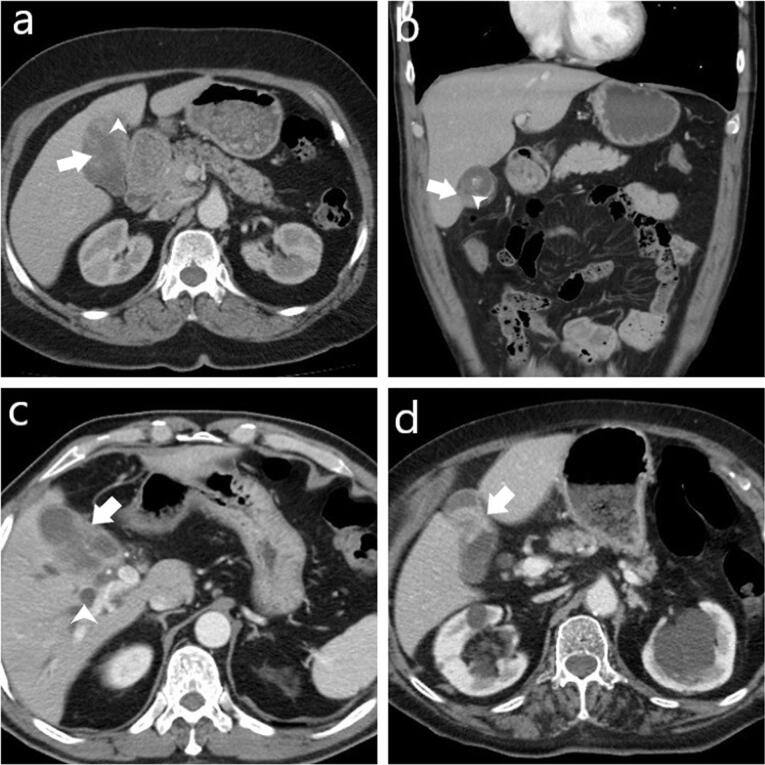

Background: Xanthogranulomatous cholecystitis (XGC) is a rare, chronic gallbladder inflammation often mistaken for gallbladder cancer (GBC) on imaging. Accurate differentiation is vital for appropriate treatment. This study aims to enhance computed tomography (CT) scan diagnostic accuracy for distinguishing XGC from GBC.

Methods: This retrospective study included patients diagnosed with XGC and GBC between 2014 and 2023. CT images of 70 patients (16 GBC, 54 XGC) were reviewed. Radiologists assessed CT parameters: gallbladder wall thickening, intramural hypoattenuating nodules, enhancement characteristics, mucosal line continuity, pericholecystic fat stranding, presence of stones, bile duct dilatation, hepatic invasion, invasion to adjacent structures, and lymph node size.

Results: Among 70 patients, there were 38 males (54%) and 32 females (46%), with a median age of 62 years. GBC patients were significantly older (median age 72 years) compared to XGC patients (60 years) (P=0.001). Diffuse gallbladder wall thickening was more frequent in XGC (70%) than GBC (12.5%) (P<0.001). Continuous mucosal lines and intramural hypoattenuating nodules were more common in XGC (P<0.001 and P=0.010, respectively). Intrahepatic bile duct dilatation and invasion to adjacent structures were significantly linked with GBC (P<0.001 and P=0.043). Lymph nodes with a short axis>8 mm indicated GBC (P<0.001), with a cutoff providing 71.4% sensitivity and 84% specificity (AUC: 0.843, P<0.001). CT showed 75% sensitivity (95% CI: 48-93%), 74% specificity (95% CI: 60%-85%), and 74% accuracy (95% CI: 62%-84%).

Conclusion: CT imaging can effectively differentiate XGC from GBC, and larger studies can further improve diagnostic accuracy.